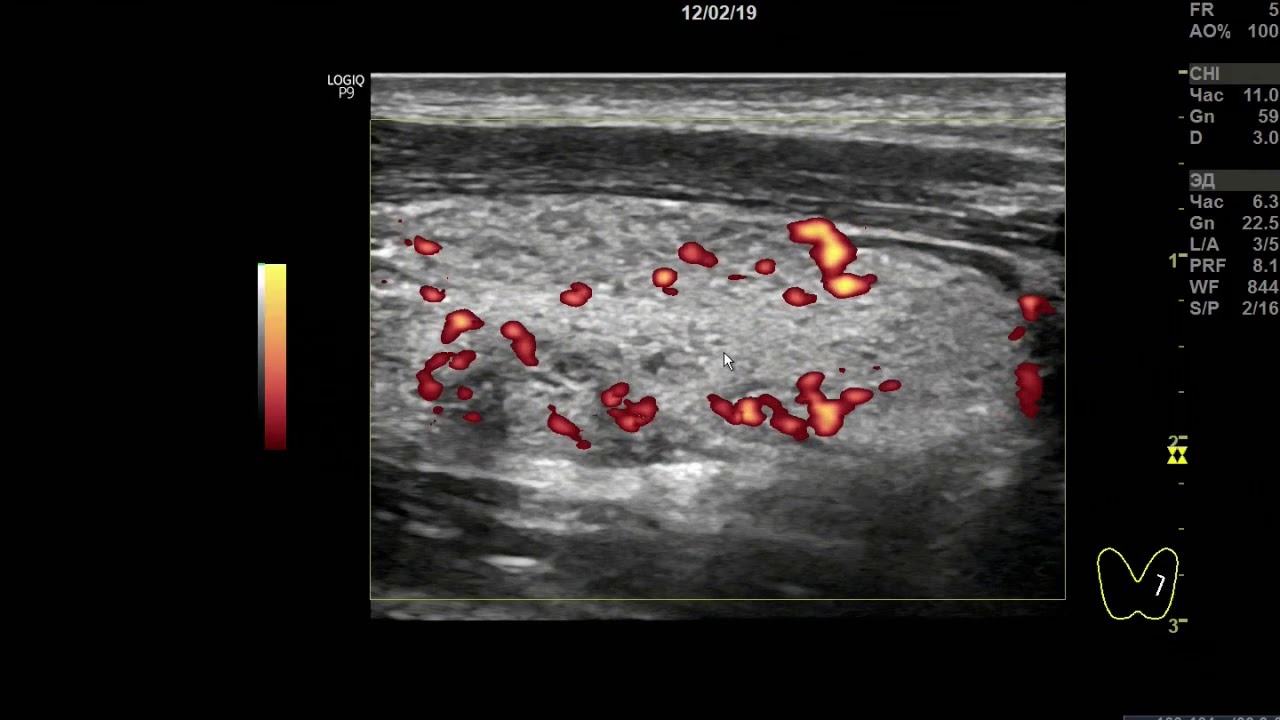

Учебный фильм - комментирует К.м.н. доктор А.В. Ушаков - главный врач Клиники Щитовидной Железы доктора Ушакова.

УЗИ диффузный процесс и зоб щитовидной железы 2 ст.

Возраст 13 лет. Тотальный диффузный зоб щитовидной железы 2 ст., со значительными явлениями крупно-долькового деструктивного преобразования,

значительной лимфоцитарной инфильтрацией, малым мелко-сегментарным

фиброзом и малой внутридольковой регенерацией. Напряжение ткани железы (по интенсивности кровотока) в малой степени усилено.